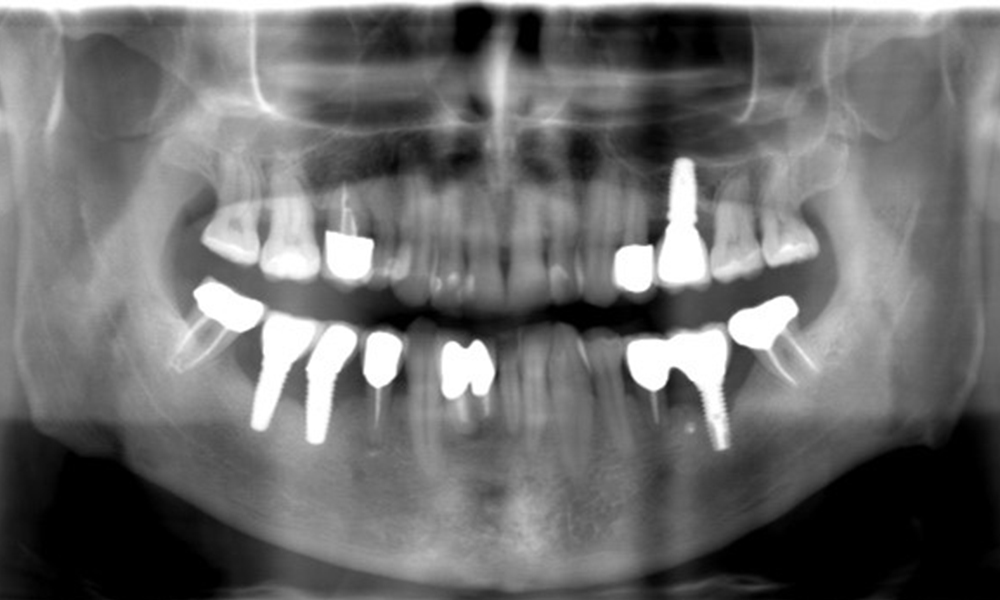

The X-ray images show the progression of bone loss.

The X-ray images show the progression of bone loss. OPG from 29.06.2020 (left) and OPG from 26.02.2024 (right).